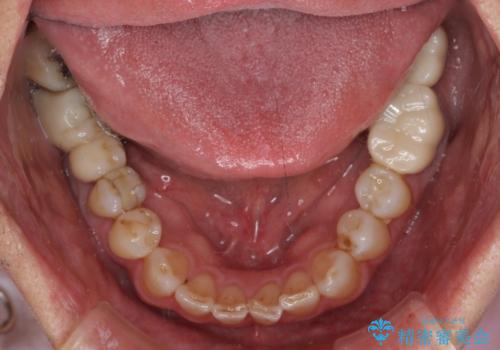

憧れの白い歯に 全顎セラミック治療

- 60歳を越え、黄ばんだ前歯をセラミッククラウンできれいな口元にしたいとのことで来院された患者様です。

診察したところ、前歯は反対咬合であり、その影響で抜歯が必要な奥歯があることが分かりました。

抜歯が必要な奥歯は、インプラント並びにブリッジにより補綴を行い、上下前歯は反対咬合を改善させるように補綴治療を行うこととしました。

健全な歯を削ってセラミッククラウンに置き換えることは、本来避けるべき治療と考えますが、今回は①患者様が60歳を越えていること、②要改善の咬合により抜歯が必要な奥歯があること、③反対咬合の前歯改善の手段としてセラミック治療が選択肢にあることなどから、全顎的なセラミック治療を行うこととしました。